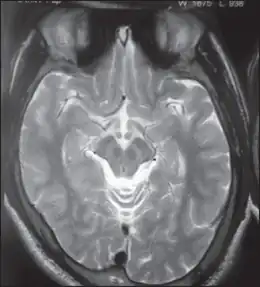

Wilson's disease may be suspected on the basis of any of the symptoms mentioned above, or when a close relative has been found to have Wilson's. Most have slightly abnormal liver function tests such as a raised aspartate transaminase, alanine transaminase and bilirubin level. If the liver damage is significant, albumin may be decreased due to an inability of damaged liver cells to produce this protein; likewise, the prothrombin time (a test of coagulation) may be prolonged as the liver is unable to produce proteins known as clotting factors.[5] Alkaline phosphatase levels are relatively low in those with Wilson's-related acute liver failure.[15] If there are neurological symptoms, magnetic resonance imaging (MRI) of the brain is usually performed; this shows hyperintensities in the part of the brain called the basal ganglia in the T2 setting.[13] MRI may also demonstrate the characteristic "face of the giant panda" pattern.[16]